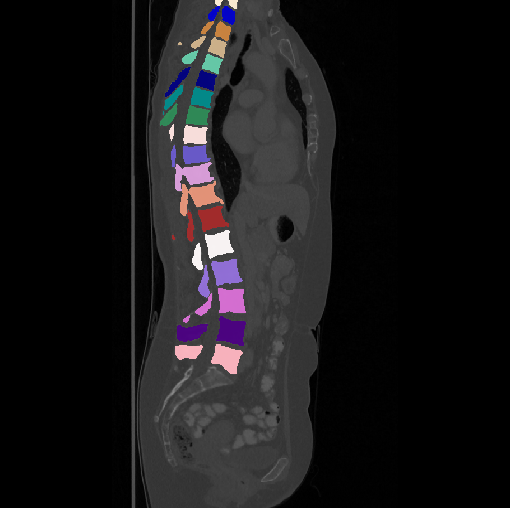

Images

GT

Predictions

We calculate the two metrics of each vertebra, and the results are reported in Table 2. On the one hand, our experimental results are close to those reported in reference (Sekuboyina et al., 2020) with the same model (nnUnet), verifying the high quality of our annotations. On the other hand, Table 2 shows it is difficult to segment the diseased vertebrae (the DSC of L6 is almost 0). Specifically, the existence of L6 confuses the model, resulting in prediction dislocations (see the last row in Fig. 4). Thus, our labeled dataset, which contains many L6 cases, is very valuable for the diseased vertebrae segmentation (we have stated those cases that are hard for annotation in the readme.txt file). Table 2 illustrates that the model trained with our annotations can achieve good performance on our CTSpine1K dataset but a much worse performance on the VerSe Challenge datasets, which explains there is an obvious domain gap between our annotated dataset and the public dataset. We infer the reason is that the COlONOG dataset is based on an empty stomach and colon, confusing the deep learning model by the changes of air content in the abdomen (see Fig. 3). Therefore, our annotations are a good complement to the existing datasets.

3.2.2 Qualitative results.

Some visualization results are presented in Fig. 4, where we can observe that the baseline model can achieve excellent segmentation results. Nevertheless, some failed predictions occur when spinal diseases exist, especially sacral lumbarization and lumbar sacralization. Besides, the image’s resolution of Z direction is closely related to the results, and a lower resolution leads to worse results. Maintaining a reasonable performance for a low resolution is a research challenge. Image superresolution (Peng et al., 2020) might be worth exploring.